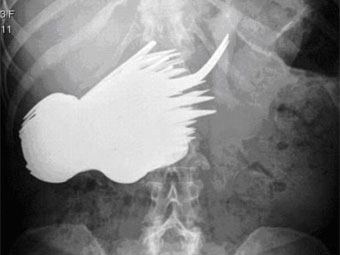

Рентгеновский снимок брюшной полости Маргарет Даалман с сайта dailymail.co.uk

52-летняя Маргарет Даалман, работающая секретарем в одном из роттердамских агентств недвижимости, попала в больницу с жалобами на боли в животе. Рентгеновское обследование показало, что в ее пищеварительном тракте находится множество посторонних предметов.

В ходе экстренной операции из живота Даалман извлекли 78 серебряных ложек и вилок. Позднее она сообщила врачам, что "захотела поесть серебра и не могла удержаться". Выяснилось, что раньше женщина уже была замечена за поеданием столовых приборов, но не в таких больших количествах.